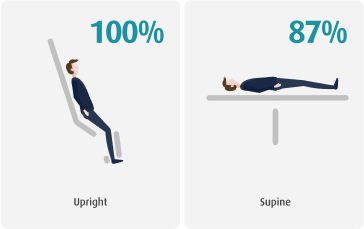

PATIENTS INDICATE UPRIGHT WILL BE MORE COMFORTABLE

PATIENT’S VIEW ON EASE OF SETUP

Patients fed back that stepping in and out of the system instead of getting up onto the table was easier in some cases.

PATIENTS FOUND IT COMFORTABLE TO BREATHE

Upright our lungs are more inflated and therefore breathing can be less laboured, meaning easier breathes.

PATIENTS FELT STABLE

Anecdotal feedback from patients suggests that when they lie on a table, they are elevated off the ground. Compared to upright they have their feet placed on the ground bringing more stability.

PATIENTS FELT COMFORTABLE

Overall patient comfort was reported to be improved upright compared to lying down on a flat table.

PATIENTS FELT IT EASY TO GET OUT OF THE SYSTEM

Patients can simply stand up from sitting and step out of the system. Which for some patients can be easier than getting up from laying down.